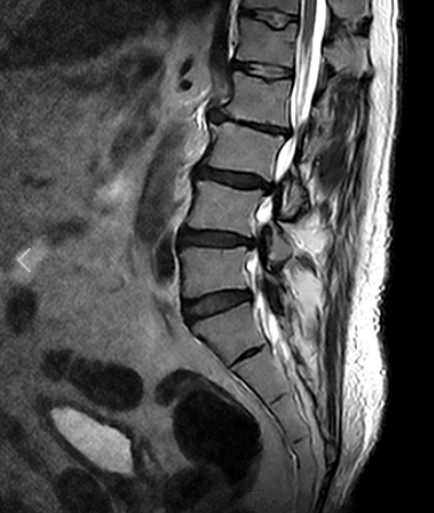

요추 염좌는 요추부의 근육이나 인대에 손상이나 과도한 늘어남이 발생하는 상황을 말합니다. 이는 많은 사람들이 경험하는 흔한 허리 부상 중 하나로, 일상 활동에 지장을 줄 수 있는 통증과 불편을 초래합니다. 이에 요추 염좌의 통증 원인과 주요 증상 4가지를 알아보고 회복 기간과 증상 완화에 효과적인 스트레칭에 대해 자세히 알아보겠습니다.

요추부 염좌 회복 기간은 부상의 정도에 따라 달라질 수 있지만 미세한 염좌의 경우, 적절한 휴식과 치료를 통해 2~4주 정도 소요될 수 있습니다. 그러나, 중등도에서 중증의 부상의 경우 몇 달이 걸릴 수 있으며, 완전히 회복되기까지 6개월 이상 걸릴 수도 있습니다.